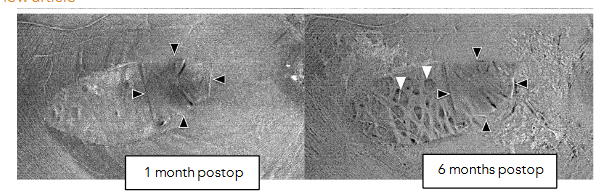

On en face OCT, they appear as multiple dark dots along the course of RNFL, called concentric macular dark spots (CMDSs), and on cross sectional OCT they appear as dimples in the inner retinal layers called dissociated optic nerve fiber layer (DONFL). CMDS were mostly found on the temporal side of the macula within two months after the ILM peeling procedure. The lesion progresses within 6 months after the surgery but remains unchanged after 12 months.

Changes in thickness of the RNFL after ILM peeling: It was found that there is an increase in RNFL thickness, only in the area nasal to fovea, where ILM was peeled, 1 month postoperatively, with subsequent reduction in thickness at 6 months postoperatively. This was attributed to the early inflammatory responses with subsequent reduction of thickness secondary to the damage inflicted to the macular retinal nerve fiber layer as a result of ILM peeling.